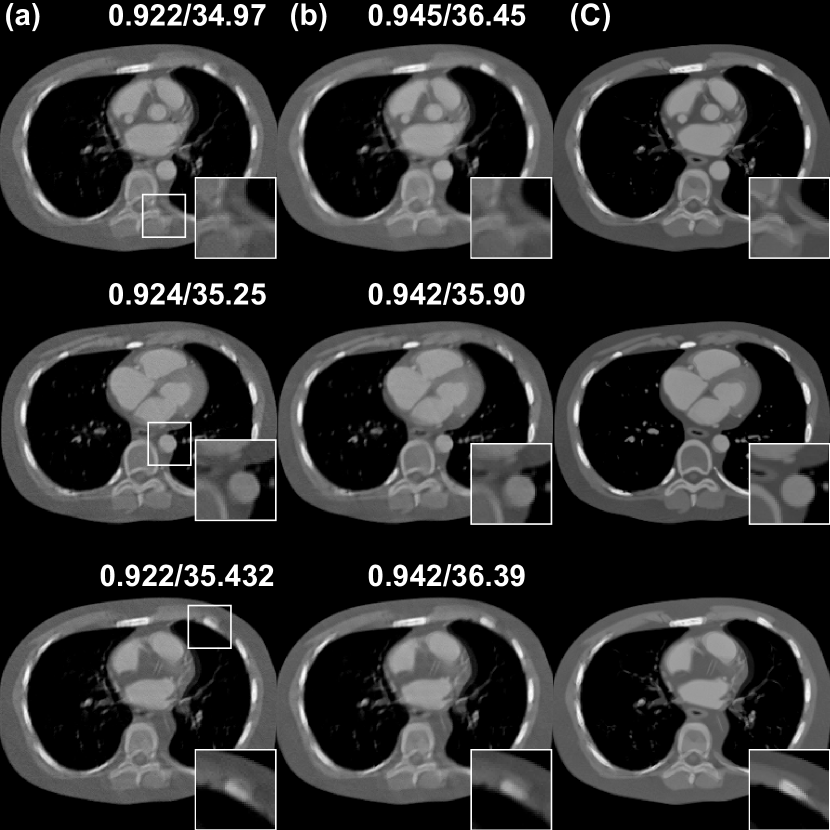

Refer to caption

Figure 7: Ablation study for the effect of TV term with 120 views using PSDM. (a) w/o TV prior, (b) w/ TV prior, (c) Ground truth. The display window is [540540-540 100010001000] HU.

Figure. 7 presents a comparative analysis of the reconstruction results with and without the TV term. These quantitative metrics (SSIM and the PSNR) indicate that the TV term can improve the perceptual quality and the fidelity of the reconstructed images. Visually, results with the TV term exhibit less noise and more consistent structural integrity compared to those without the TV prior. Figure. 8 illustrates the performance comparison between PSDM and Diffusion-MBIR with respect to numbers of reverse diffusion steps. It is observed that PSDM demonstrates faster convergence relative to Diffusion-MBIR. Specifically, in the iterations ranging from 600 to 800, Diffusion-MBIR exhibits higher noise levels compared to PSDM. Figure 9 provides a quantitative comparison of the performance with and without the Fourier fusion module. It is observed that between 400-800 reverse steps, the PSDM (presumably a metric being compared) with the Fourier fusion module outperforms the one without it. Ultimately, both the PSNR and SSIM metrics show a slight improvement when the Fourier fusion module is utilized, highlighting its benefits.